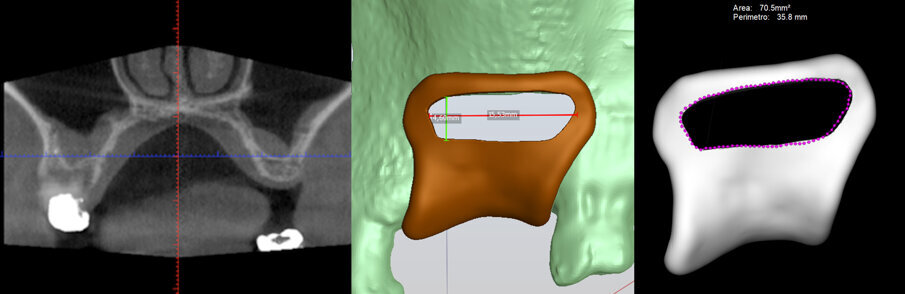

Il paziente si è presentato all’attenzione del chirurgo richiedendo la riabilitazione del mascellare superiore sinistro, privo degli elementi 2.5 e 2.6 (Figg. 2, 4). Dopo valutazione clinica e radiografica, anche attraverso CBCT, al paziente è stato proposto un piano di riabilitazione impianto-protesica basato sull’esecuzione di un rialzo di seno attraverso la tecnica Low Window ed il contestuale inserimento di due impianti osteointegrati. Il paziente ha fornito il proprio consenso informato al trattamento. Le scansioni CBCT sono state utilizzate per pianificare sia la posizione dell’inserimento dei due impianti, sia la posizione e il disegno della finestra di accesso laterale secondo i principi della tecnica Low Window (Fig. 3). Utilizzando un opportuno software (Realguide, 3diemme, Cantù), infatti, è stata progettata una dima chirurgica che incorporava una apposita guida per permettere di delimitare intraoperativamente il disegno della finestra di accesso. La dima è stata quindi fabbricata attraverso un sistema standard di stampa in tre dimensioni (Mech & Human, Lissaro).

Fig. 3 - La posizione degli impianti viene pianificata sulla scansione CBCT. La progettazione include il disegno di una dima chirurgica che include la guida per disegnare l’antrostomia in accordo con i principi della tecnica Low Window.